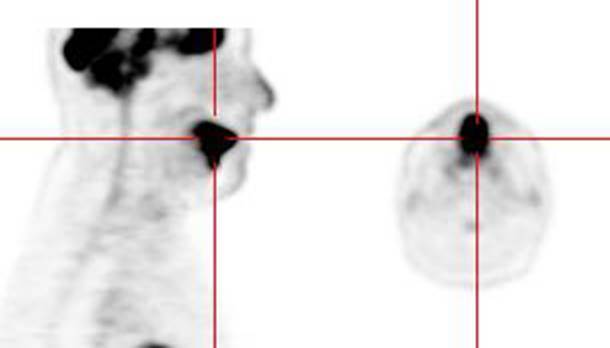

Figure 11 - Brown Fat: Prominent, symmetric

supraclavicular tracer uptake was seen in this patient without a corresponding

CT finding. Uptake in this area has been felt to be related to the presence of

"brown" fat.